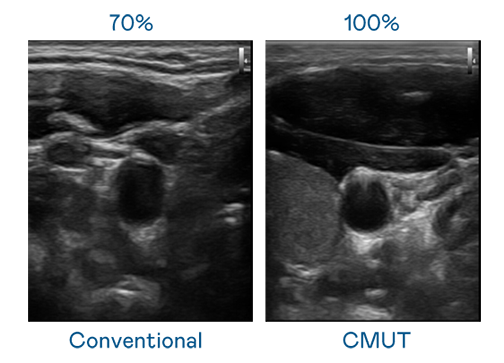

CMUT 技术是一种用电容式微机电元件来产生超音波讯号的技术。与传统 PZT 压电式技术相比,CMUT 频宽增加 30%,更宽频的超音波讯号让影像解析度大幅提升,是实现高影像品质医疗超音波扫描、促进精准医疗发展的关键技术。

大频宽带来超清晰影像

超音波影像的解析度高低,首先取决于探头能发出的讯号频宽。AG亚游 CMUT 可提供高清晰的超音波讯号,提供高频宽、高灵敏度、影像纹理细节更高的超音波影像,协助医护人员缩短影像判读时间及利用精准的医疗影像进行诊断。